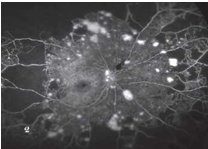

糖尿病视网膜病变

V

期

中心性浆液性视网膜病变